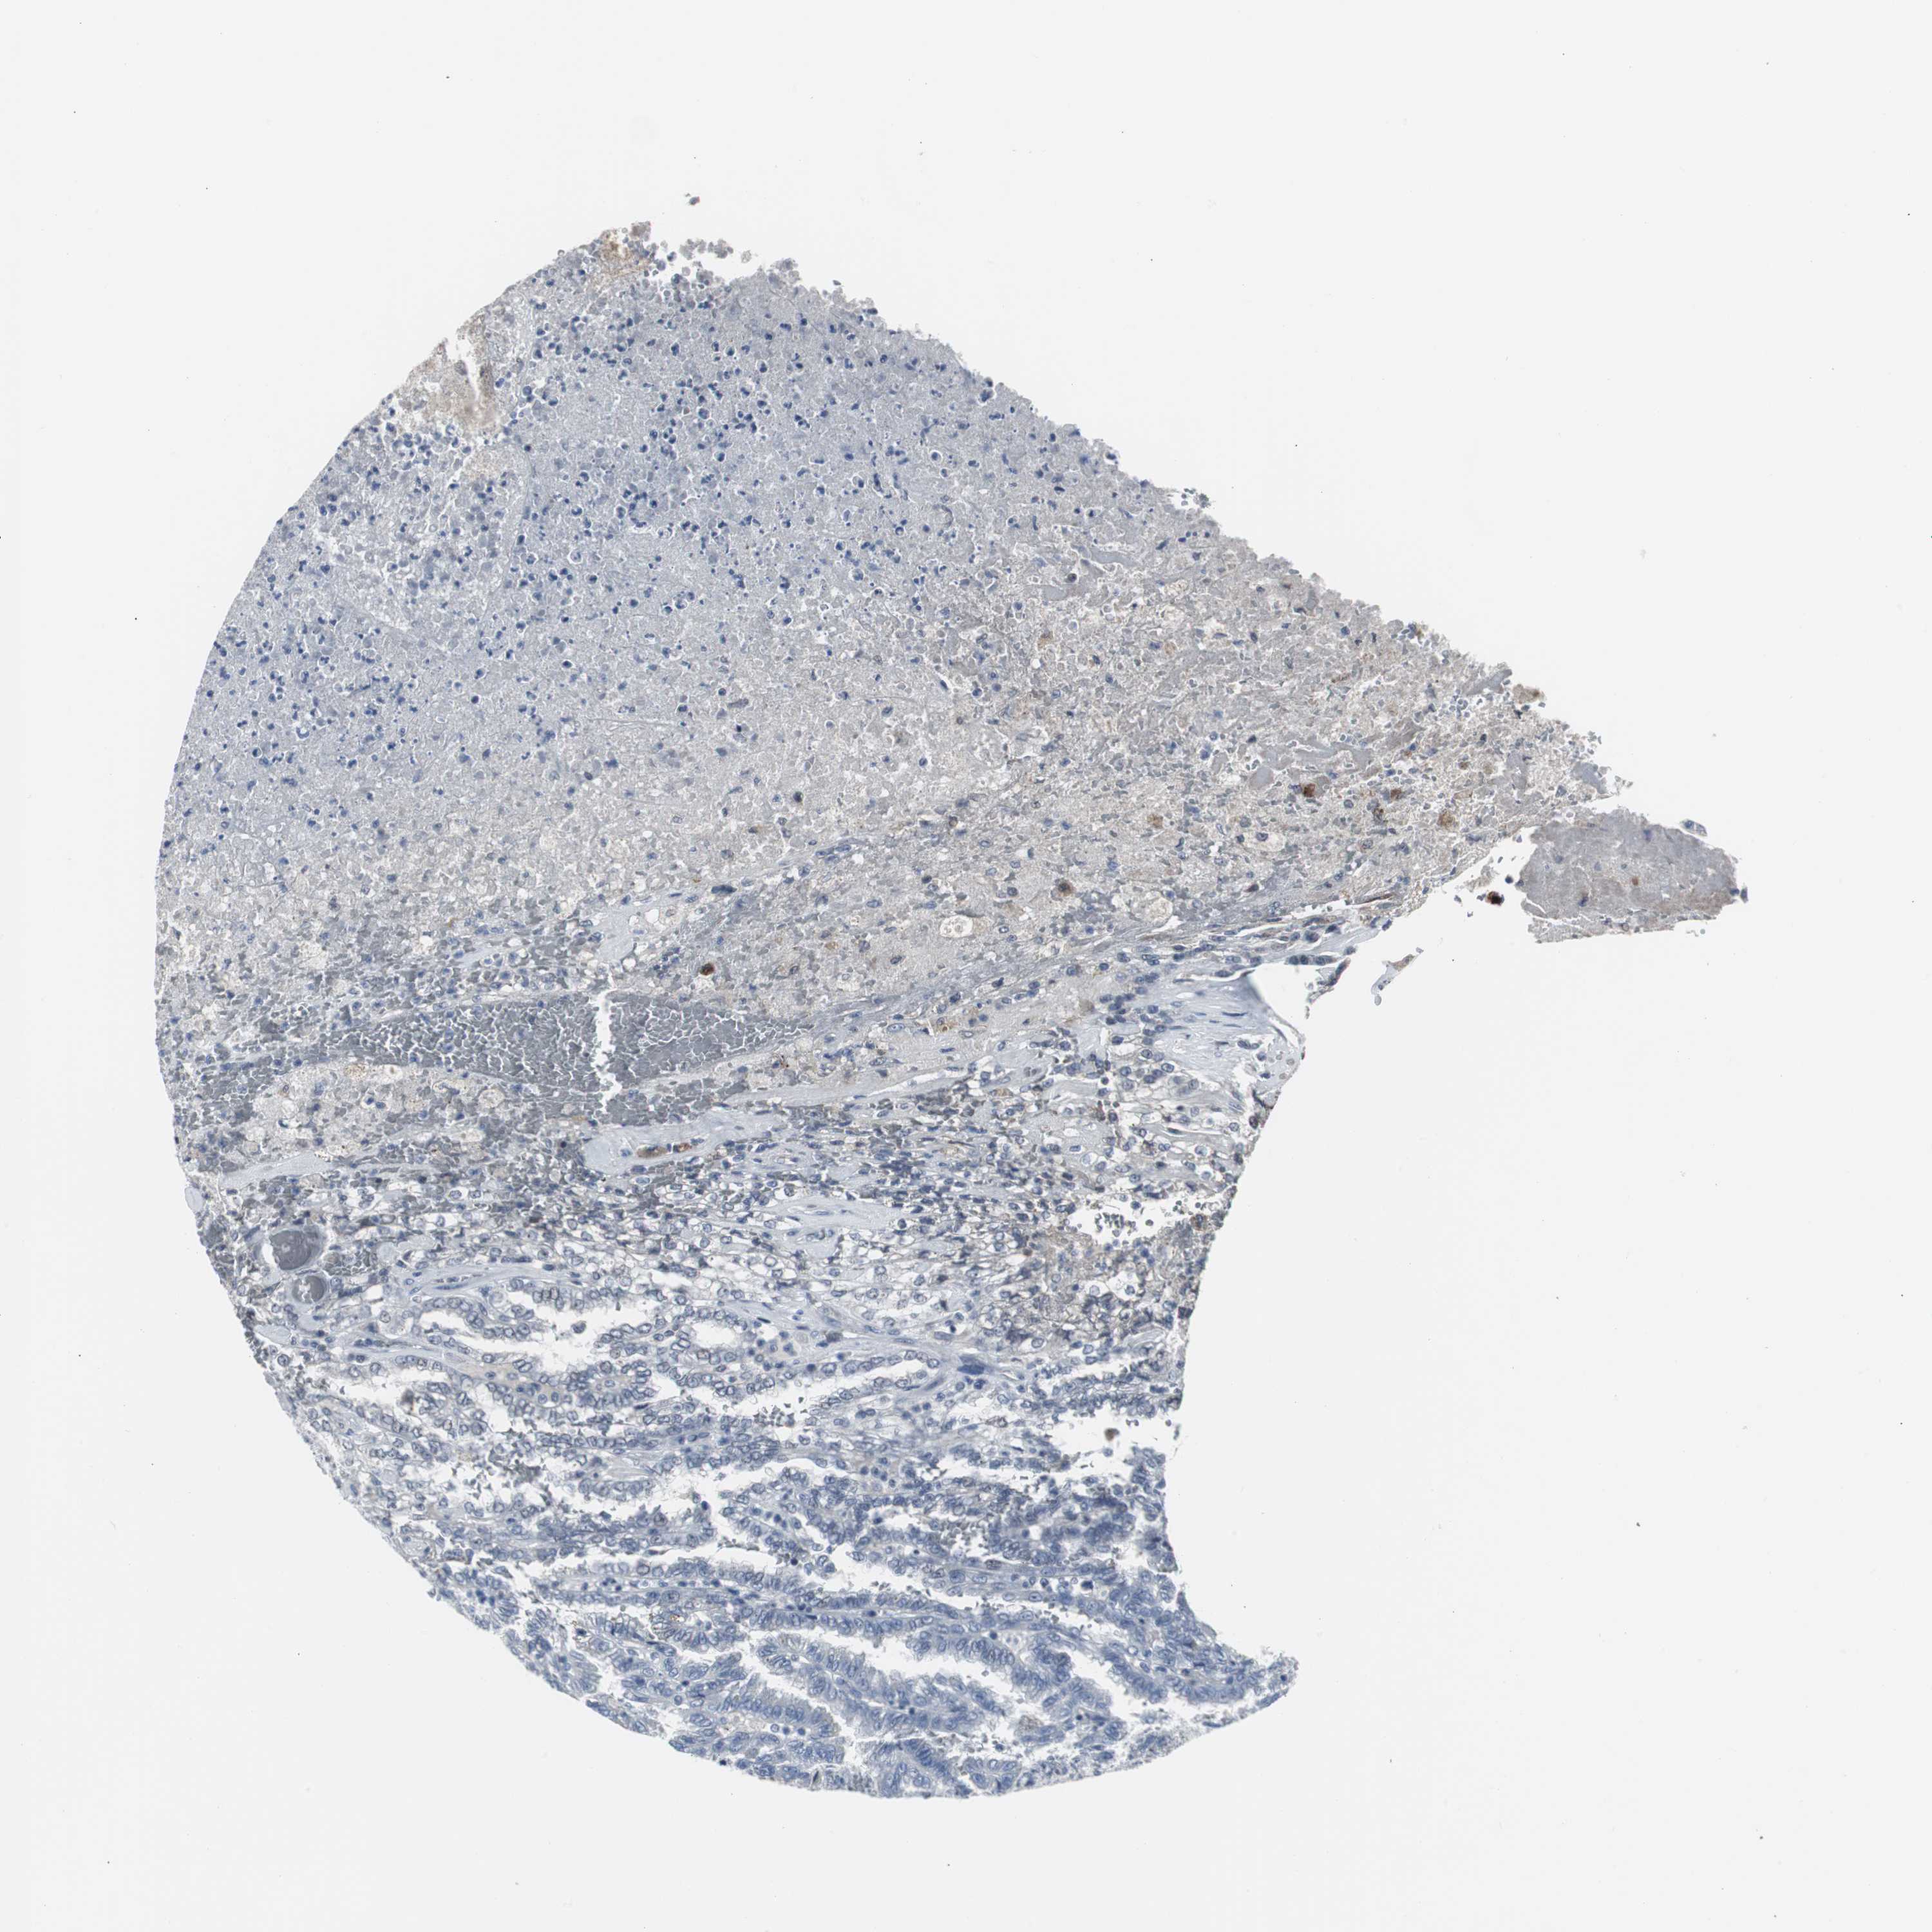

CANCER RENAL CANCER Show tissue menu

KICH TCGA KIRC TCGA KIRC VALIDATION KIRP TCGA PROTEIN RCC CPTAC PROTEIN EXPRESSION

KIDNEY CHROMOPHOBE (TCGA) - Interactive survival scatter ploti

The Survival Scatter plot shows the clinical status (i.e. dead or alive) for all individuals in the patient cohort, based on the same data that underlies the corresponding Kaplan-Meier plots. Patients that are alive at last time for follow-up are shown in blue and patients who have died during the study are shown in red.

The x-axis shows the expression levels (FPKM) of the investigated gene in the tumor tissue at the time of diagnosis. The y-axis shows the follow-up time after diagnosis (years). Both axes are complimented with kernel density curves demonstrating the data density over the axes. The top density plot shows the expression levels (FPKM) distribution among dead (red) and alive patients (blue). The right density plot shows the data density of the survived years of dead patients with high and low expression levels respectively, stratified using the cutoff indicated by the vertical dashed line through the Survival Scatter plot. This cutoff is automatically defined based on the FPKM cutoff that minimizes the p-score. The cutoff can be changed by dragging the vertical line or by entering a cutoff value in the square labeled "Current cut-off".

Under the Survival Scatter plot the p-score landscape (black curve; left axis) is shown together with dead median separation (red curve; right axis). Dead median separation is the difference in median mRNA expression between patients who have died with high and low expression, respectively. It is calculated as follows: median FPKM expression of dead patients with high expression - median FPKM expression of dead patients with low expression. This is intended to aid the user in visually exploring custom cutoffs and the associated p-scores and dead median separation.

Individual patient data is displayed and can be filtered by clicking on one or more of the category buttons on the top of the page. Categories describing expression level and patient information include: high, low, alive, dead, female, male and tumor stages. The scale of the x-axis can be toggled between linear and log-scale by clicking on the "x log" button. Mouse-over function shows TCGA ID, patient information and mRNA expression (FPKM) for each patient.

& Survival analysisi

Kaplan-Meier plots summarize results from analysis of correlation between mRNA expression level and patient survival. Patients were divided based on level of expression into one of the two groups "low" (under cut off) or "high" (over cut off). X-axis shows time for survival (years) and y-axis shows the probability of survival, where 1.0 corresponds to 100 percent.

DOK1 is not prognostic in Kidney Chromophobe (TCGA)